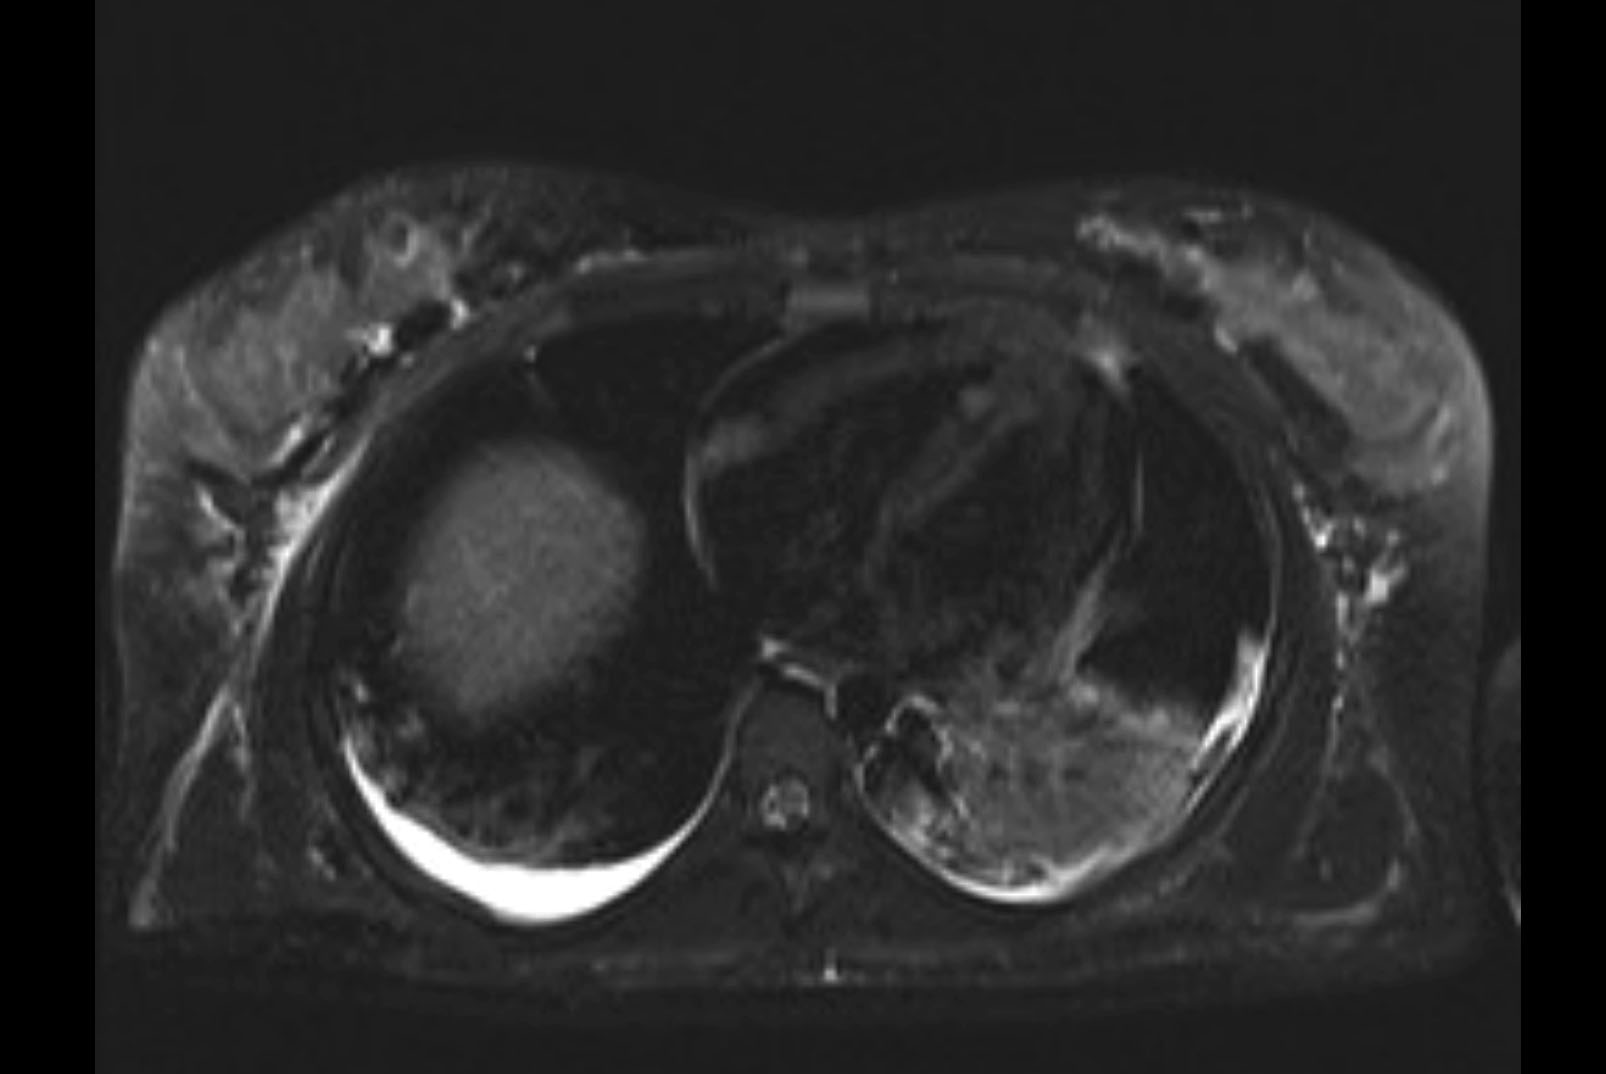

MRI T1

MRI T2